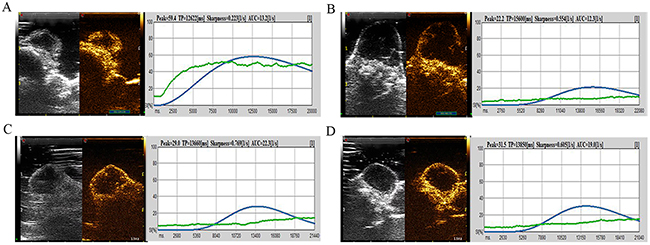

DCE-US was performed before HIFU irradiation and at 24 hours, 48 hours, and 2 weeks after irradiation in the sub-ablation group. Four DCE-US perfusion parameters were computed as shown in Table 3. Correlation between tumor size and US perfusion parameters was analyzed. DCE-US perfusion parameters, including peak intensity (PI) (58.3 ± 7.1 vs. 20.4 ± 5.2), area under the curve (AUC) (13.2 ± 3.2 vs. 11.3 ± 4.1), had decreased 1 day after irradiation. In addition, TP (12532.7 ± 34.9 vs. 15721.4 ± 54.2) and sharpness (0.24 ± 0.1 vs. 0.54±0.2) increased at 24 hours after irradiation. However, PI and AUC increased at 48 hours and 2 weeks after irradiation compared with 24 hours after irradiation. Time to peak (TP) decreased compared with those of the 24-hours group.

CEUS images and DCE-US time-intensity curves of one mouse in Group B at different times, before and after irradiation, are shown (Figure 5). In Figure 6, the blue line with the highest PI and least TP shows the DCE-US time-intensity curve before HIFU irradiation. The red line with the lowest PI and longest TP reflects the intensity of the ultrasonic image changing over time at 24 hours after HIFU irradiation. The green line and the purple line show the time-intensity curve at 48 hour and 2 weeks after HIFU irradiation, respectively, which are smoother than the blue line.

Figure 5: CEUS image and DCE-US time-intensity curves of one mouse in Group B at different times before and after irradiation. (A) The CEUS image and DCE-US perfusion parameters before HIFU irradiation. (B) The CEUS image and the intensity of ultrasonic image changing over time at 24 hours after HIFU irradiation. (C) Perfusion parameters at 48 hours after HIFU irradiation. (D) Time-intensity curve at 2 weeks after HIFU irradiation.

As shown in this study, HIFU (Group C, 65°C-80° C) and sub-threshold HIFU (Group B, 55°C-60° C) inhibits tumor growth. Three tumors in Group C disappeared, with seven mice skin burned. In Group B, all tumors showed inhibited growth, with no mice skin burned. The US perfusion parameters, including PI and AUC, had decreased significantly 24 hours after irradiation (P <0.05) in Group B. TP and sharpness had increased significantly 24 hours after irradiation because the tumor was ablated and the volume of the tumor was reduced. At the late phases of irradiation, PI and AUC increased and TP decreased at 48 hours and 2 weeks after irradiation compared with 24 hours because the tumor had grown larger and microvascular increased. As shown in Figure 6, the red line with the lowest PI and longest TP at 24 hours after HIFU irradiation might reflect the best efficiency of sub-threshold HIFU radiation. Because of the tumor growth and blood vessel density inside the tumor increased, green line and the purple line are both above the red line. These results suggest that the US perfusion parameters are useful for predicting the therapeutic response after irradiation.